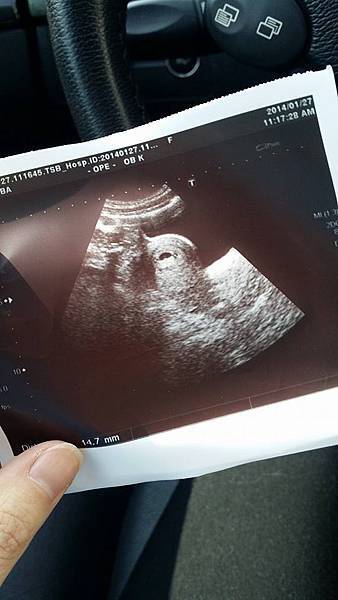

照到囉!!!!!

小寶貝著床囉~

一個小小的豆子是個小生命耶!!!